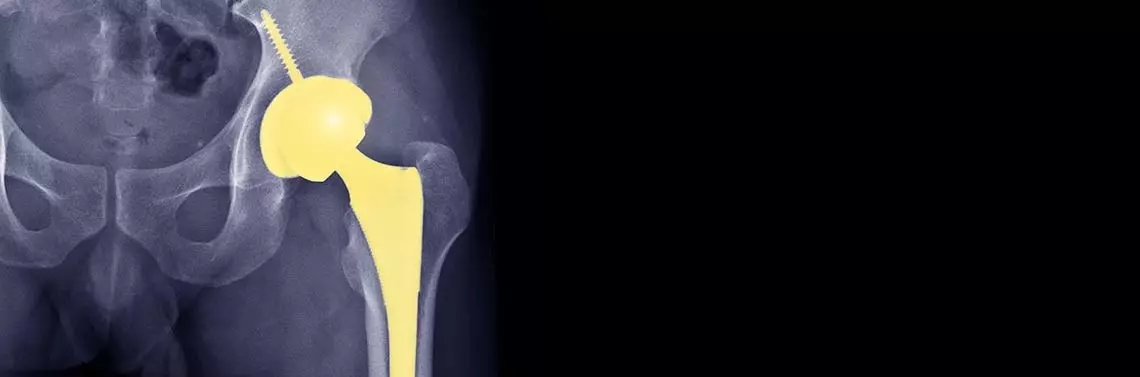

Głównym celem leczenia zmian zwyrodnieniowych jest uśmierzenie dolegliwości bólowych i zwiększenie zakresu ruchomości kończyny, i dzięki temu umożliwienie pacjentowi wykonywania samodzielnie czynności codziennych, co prowadzi do znaczącej poprawy jego jakości życia [2]. Rewolucyjną metodą leczenia, poprawiającą sytuację pacjentów ze zmianami zwyrodnieniowymi w stawie biodrowym, była endoprotezoplastyka. Ta metoda leczenia swoimi początkami sięga aż XIX wieku, natomiast nowoczesną formę zyskuje od lat 40. XX wieku i jest ona stale udoskonalana [3]. Wraz z poprawą metody leczenia również wskazania do niej uległy znacznemu poszerzeniu. W dzisiejszych czasach endoprotezoplastyka jest proponowana pacjentom tylko i wyłącznie w przypadku wieloletniej niepełnosprawności stawu biodrowego, którego choroba rzutuje na cały układu ruchu, ale bywa również wykonywana przed wystąpieniem zmian kompensacyjnych, np. w kręgosłupie czy stawach kolanowych. Między innymi dzięki takiemu podejściu, w połączeniu z dostępnością implantów najnowszej technologii, leczenie operacyjne choroby zwyrodnieniowej jest w stanie przynieść satysfakcjonujące rezultaty nawet najbardziej wymagającym pacjentom [4].